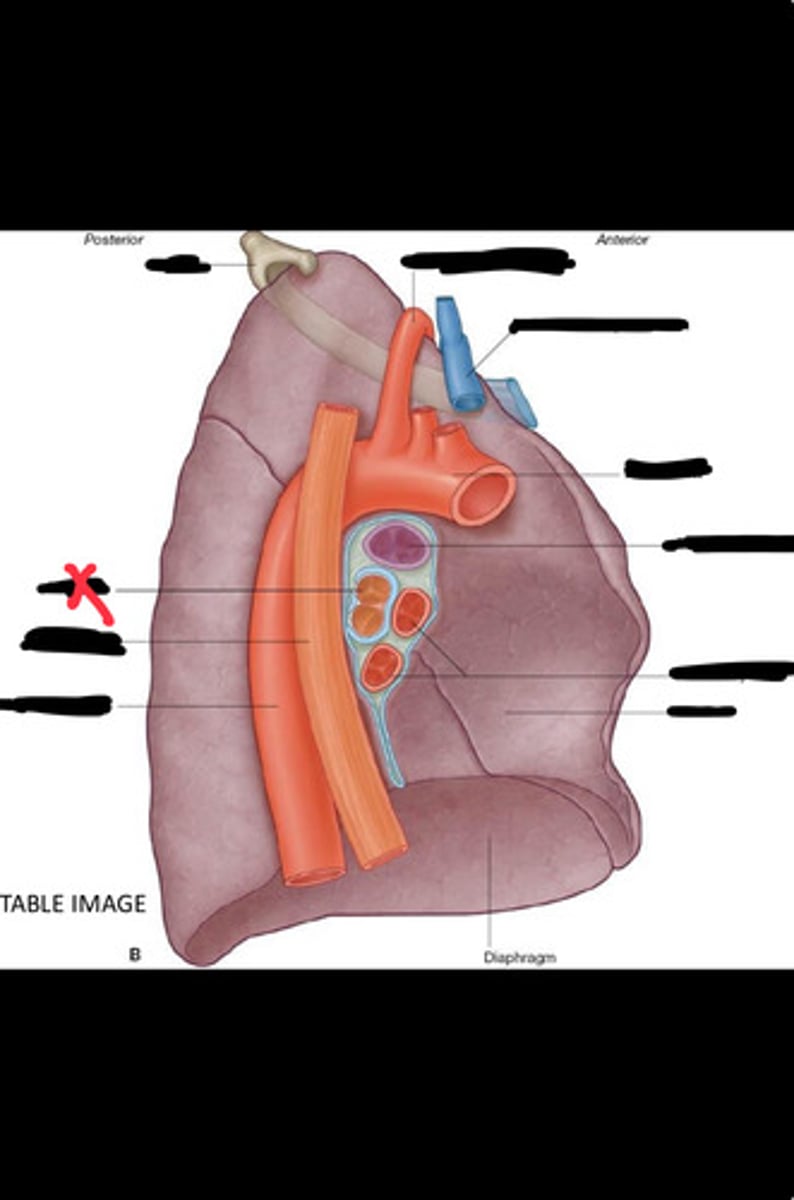

Diaphragm

Inferior vena cava

Superior vena cava

Subclavian vein

Right bracheocephalic vein

Subclavian artery

Esophagus

Bronchus

Rib 1

Left subclavian artery

Left brachiocephalic vein

Aortic arch

Pulmonary artery

Pulmonary vein

Heart

Left brachiocephalic vein

Azygos vein

Esophagus

Bronchus

Fibrous pericardium

Parietal layer of serous pericardium

Pericardial cavity

Visceral layer of serous pericardium

Junction between fibrous pericardium and adventitia

Heart

Thoracic aorta

Rib 1

Pulmonary artery

Bronchus to superior lobe